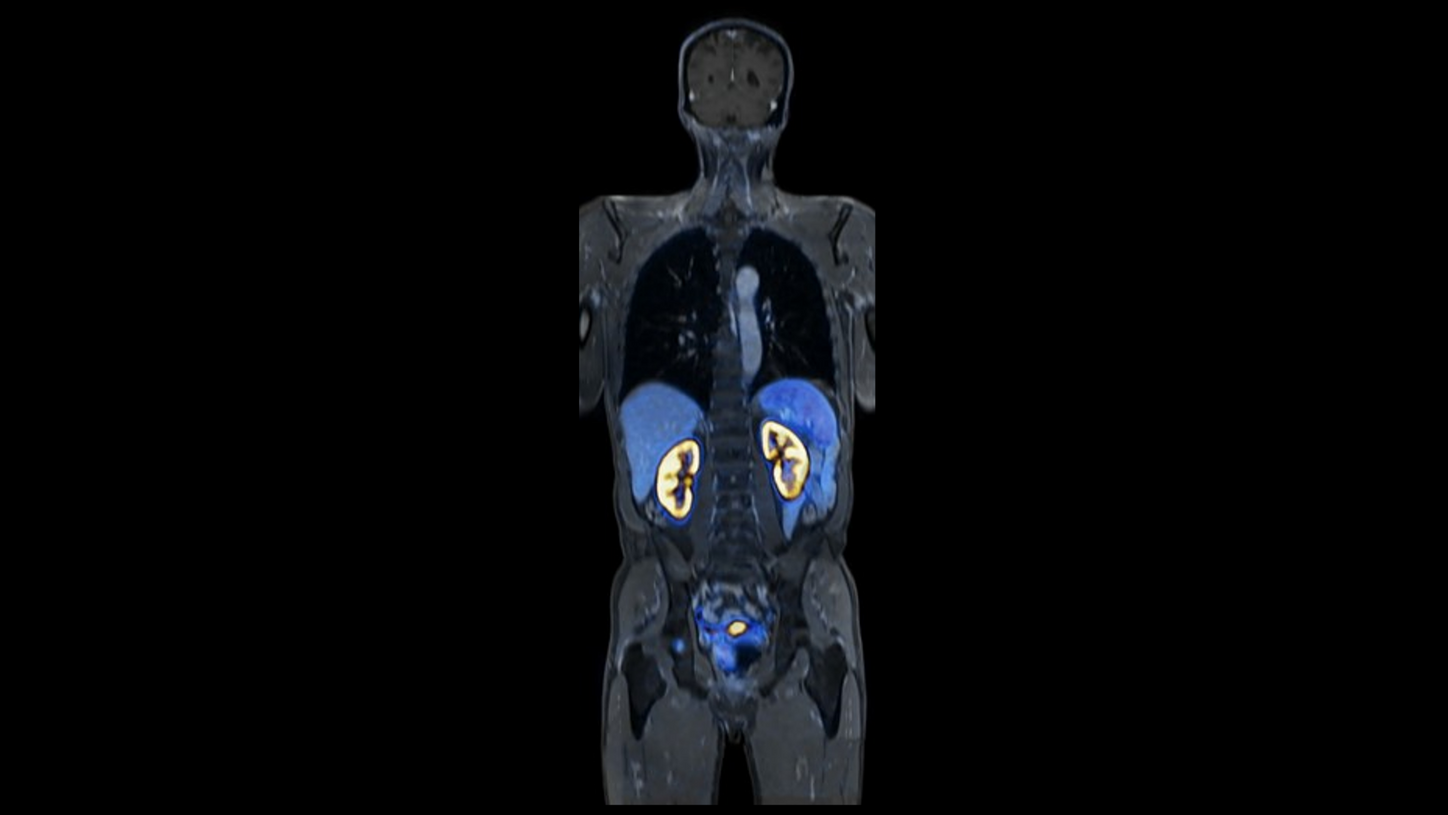

BIOGRAPH One is designed to support one patient-centric pathway to personalized care. By seamlessly integrating PET and MR into one comprehensive exam, it will support clinicians from diagnosis and staging, through a personalized therapy decision to regular therapy assessments to excel precision and support one streamlined approach.

BIOGRAPH One is designed to excel in PET/MR precision to support confident diagnostic decisions. Featuring the Optiso UDR Pro detector with the largest 35 cm axial FOV2 in PET/MR, it is designed to enable comprehensive capture with excellent sensitivity and ultra-fast TOF3 in real time – delivering clear, detailed images.

Planned with Deep Resolve for accelerated acquisition and improved resolution in 2D and 3D applications4, BIOGRAPH One has the potential to make PET/MR exams faster than ever before. Designed with a powerful 3T magnet at its heart, BIOGRAPH One will deliver unparalleled performance with outstanding homogeneity, a large 55 x 55 x 50 cm³ field of view and robust gradient power.